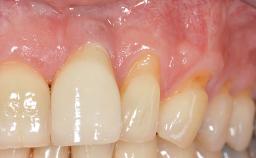

GBR and Soft-Tissue Augmentation Following Explantation to Rehabilitate a Soft- and Hard-Tissue Defect

It is sometimes necessary to remove and replace compromised implants. This case is a clear example of the need for multiple steps to achieve an optimal therapeutic result for patients with non-salvageable implants. It illustrates how the lost soft and hard tissues were rebuilt in a sequence that improved the healing of the hard tissues and assured their long-term stability. The 35-year-old healthy patient presented with clinical attachment loss on the proximal and lingual surfaces of the natural dentition. Some gingival recession was present on natural teeth, particularly in the posterior sextants (S1, S3, S4, and S6).